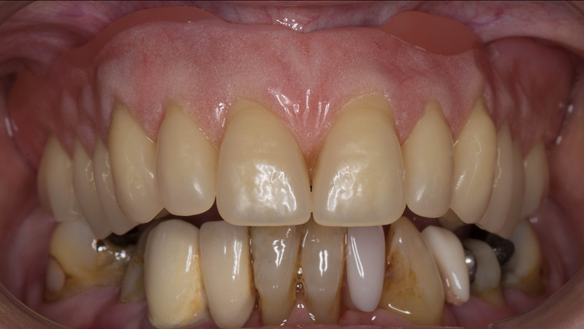

This newsletter describes in step by step detail Anne's transition from an immediate complete upper denture to a definitive complete upper denture.

This 73 year old woman was referred to me by her general dental practiioner for treatment.

- The remaining natural upper natural teeth and lower back molars were heavily restored having generalised periodontitis stage 4 Grade C. Some of the teeth exhibited caries. The prognosis for these teeth ranged from dubious to hopeless.

- The lower teeth (apart from the lower back molars) had better progniosis and were to be managed by the referring general dental practitioner.

- The upper and lower acrylic based partial dentures exhibited suboptimal extension of the flanges and saddles. They had poor retention, support, stability and tissue fit.

- The patient had a high smile line showing 5mm or more alveolar soft tissue above the upper front teeth during social interaction.

The clinical situation and treatment process is shown in detail below with photographs. In addition, threre is a link to the a 45 minute webinar I gave explaing this case. I provided the clinical work and Rowan Garstang provided the technical work.